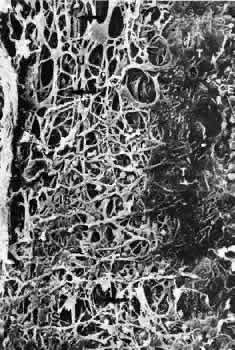

Scanning electron micrographs of serial layers through the entire meshwork and tangential sections (parallel to the inner wall of Schlemm's canal) reveal that the form of the trabecular lamellae and of the intertrabecular spaces changes markedly from the inner to the outer portions of the meshwork. The innermost iridial meshwork consists mostly of long, radial, interconnecting strands forming an irregularly arranged network with rather large openings (Figs. 3 and 4). In the uveal portion, flat sheets are evident that are still relatively irregularly arranged but frequently interconnect with each other. The holes within the uveal meshwork are somewhat smaller than in the iridial meshwork but still show diameters varying between 10 and 30 μm.

Toward Schlemm's canal the corneoscleral meshwork is more expanded and forms broad lamellae that run predominantly in an equatorial direction (Fig. 5). The trabecular lamellae interconnect with each other and are regularly arranged. The intertrabecular spaces appear now as elongated rhomboid-like pores, the long diameter of which averages 10 to 20 μm.7